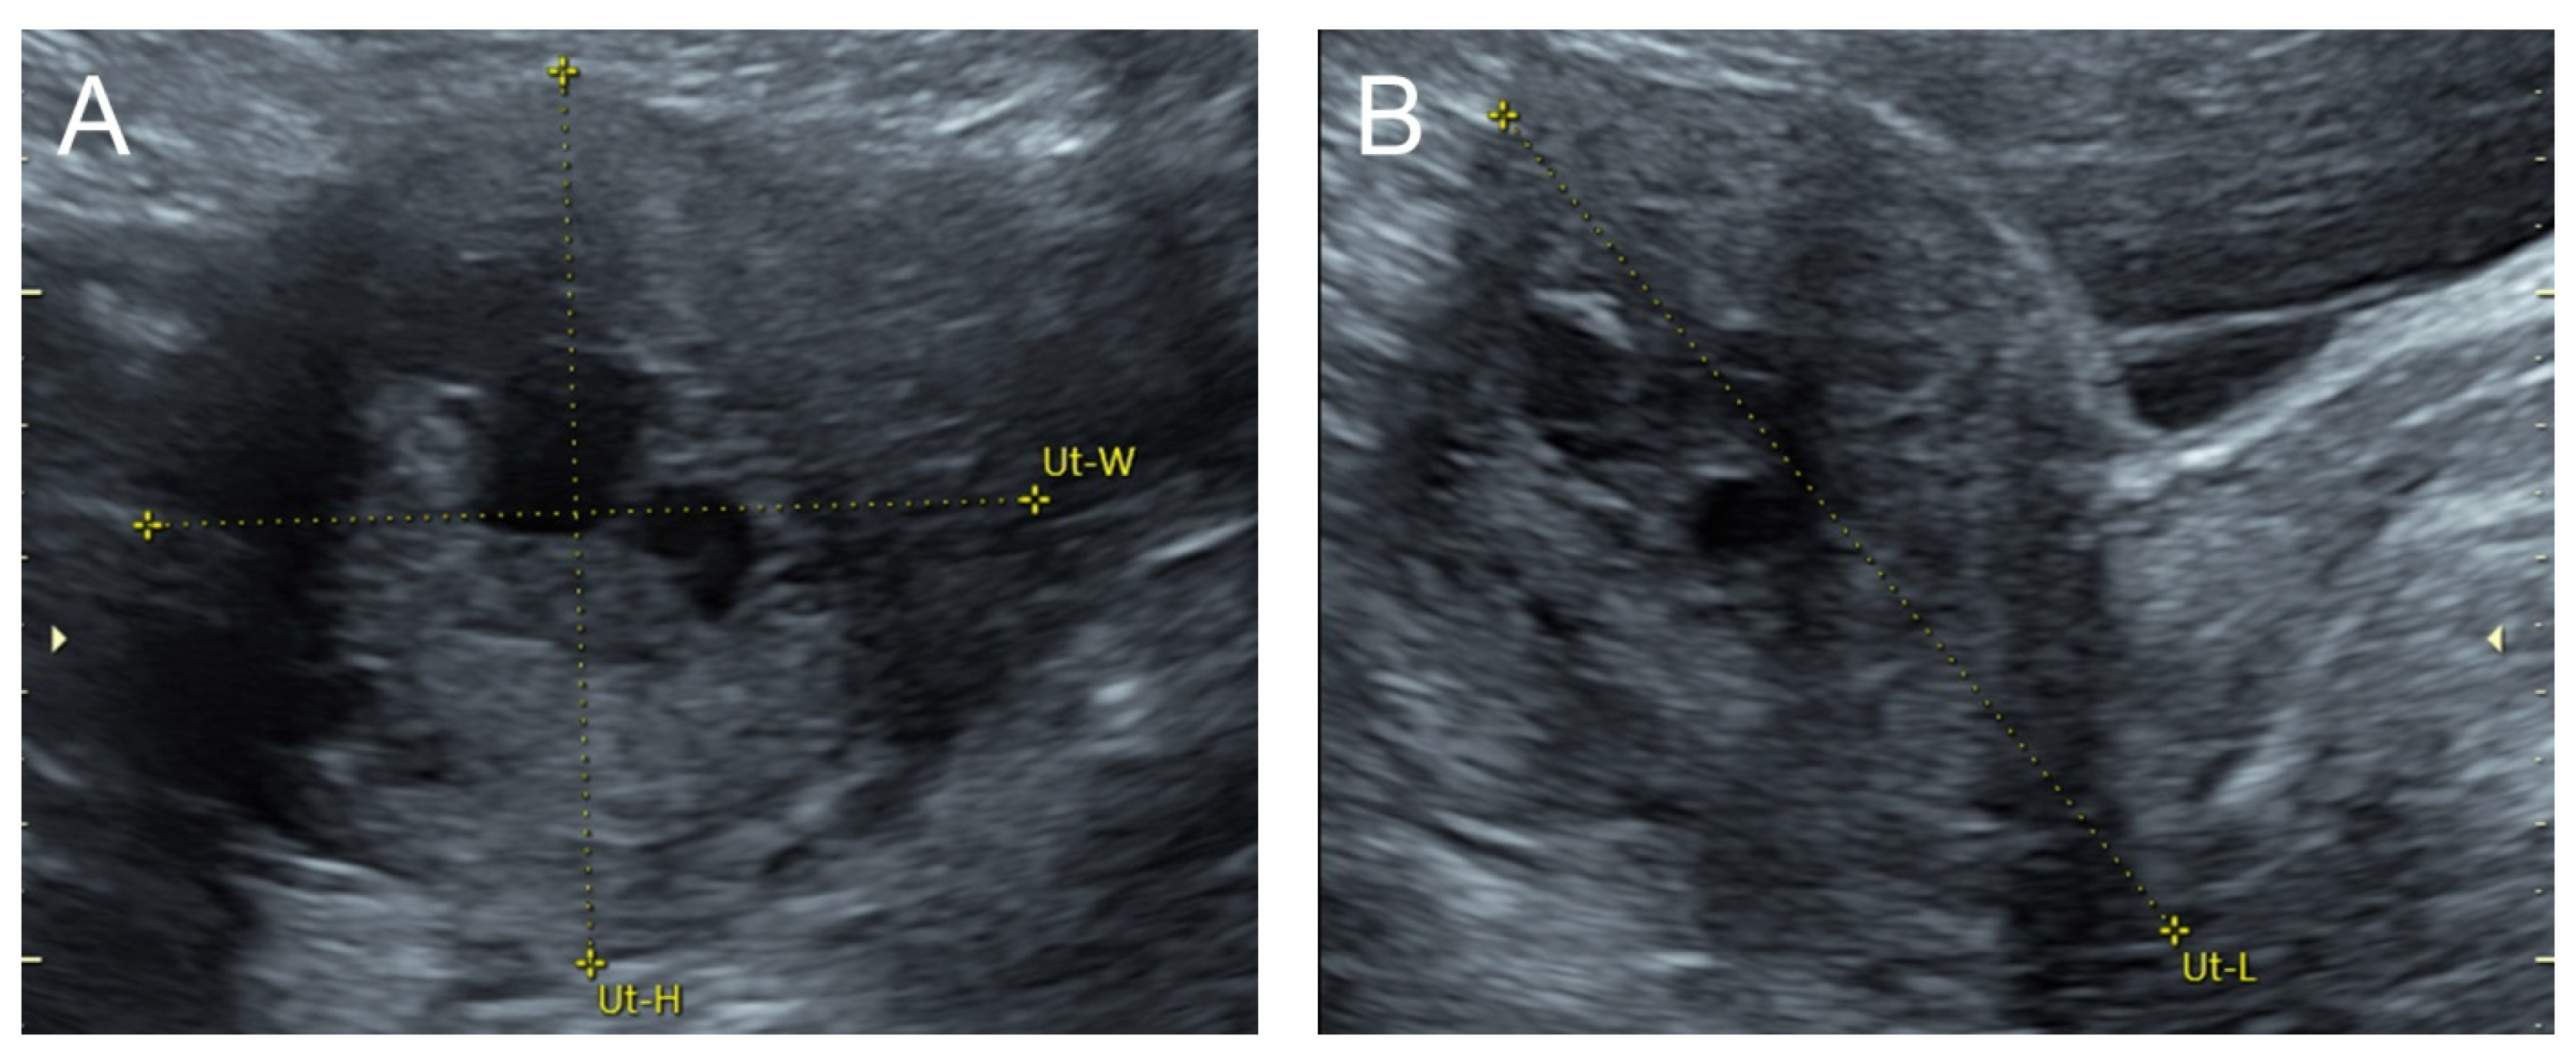

Figure 2.

(A) Transabdominal grayscale ultrasound: transverse scans of suprapubic area showed suboptimal-quality image of the uterus, which displayed ill-defined soft tissue mass, non-visualized endometrial lining, hypoechoic areas of the uterus. No normal architecture of the uterus could be demonstrated. (B) Color flow mapping (the same area of figure (A)) showed markedly vascularized uterus, involving throughout the uterus intense vascularity with a chaotic, multidirectional flow. (C) Transvaginal color Doppler ultrasound showed markedly vascularized uterus, involving throughout the uterus intense vascularity with a chaotic, multidirectional flow. (D) Abdominal CTA revealed innumerable tortuous dilated vessels in the pelvic cavity, along the entire uterine wall. The lesions were fed by multiple arterial feeders, which were displayed as tortuous dilated arteries of the bilateral uterine arteries, right ovarian artery, and right inferior epigastric artery. Multiple draining veins demonstrated early venous opacification, namely the bilateral internal iliac veins and right ovarian vein. The CTA findings confirmed uterine AVM.